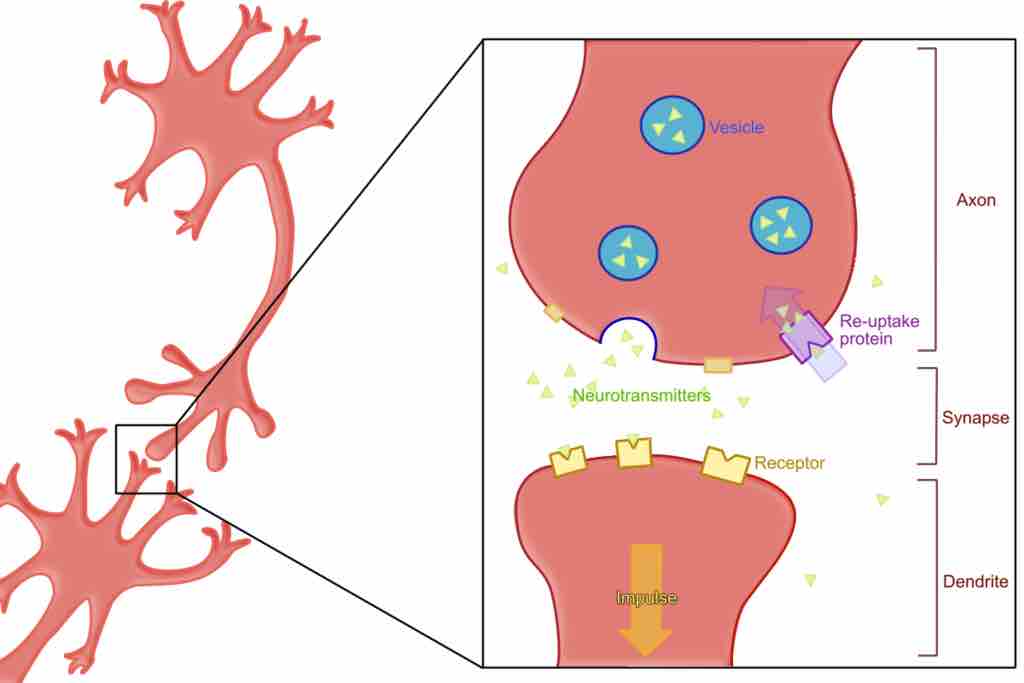

Neurotransmitters

The reuptake process

This illustration shows the process of reuptake, in which leftover neurotransmitters are returned to vesicles in the presynaptic cell.